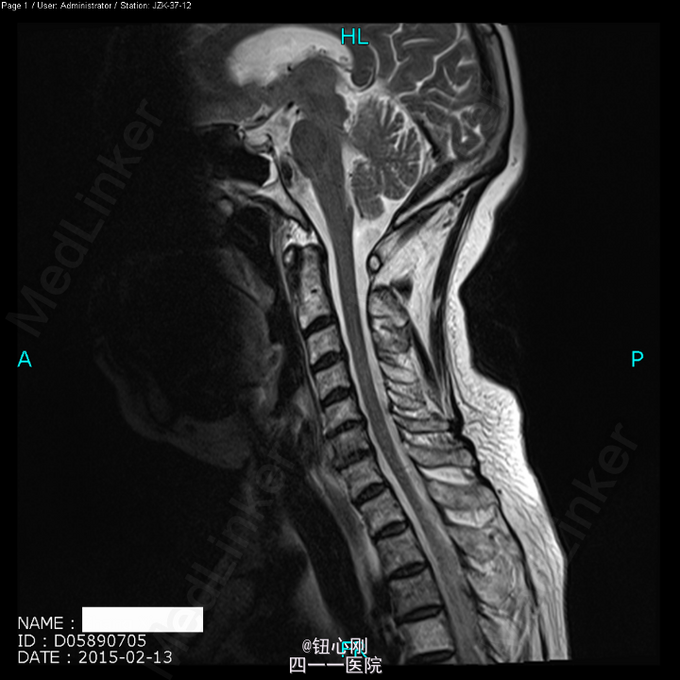

体检未见明显阳性体征。 辅助检查:血沉68mm/h,神经元特异性烯醇化酶23ug/l,余肿瘤指标正常。三大常规、肝肾功、电解质正常。 颈椎MRI、腰椎MRI及PET-CT扫描见图。

术前诊断:多椎体病变待查(转移瘤?) 诊断依据:老年女性,出现颈腰部疼痛,MRI及PET-CT扫描提示椎体多节段病变,以转移瘤可能性为大,同时血沉升高。 处理:2015-03-31在全麻下行颈6椎体病变前路次全切+钢板钛网植骨融合内固定术。术中所见:颈6椎体骨质疏松,部分硬化,未见鱼肉样组织。术后切除骨质送病理检查。 病理报告:骨小梁稀疏,其间有纤维组织,同时可见硬化死骨。 术后诊断:颈6椎体骨质疏松性骨坏死。

随着医学影像学及脊柱微创手术的发展,骨质疏松性椎体骨坏死逐渐被认识。该病临床上并非少见,骨坏死会导致椎体逐渐塌陷与进行性后凸畸形,引起患者长期腰背痛,甚至出现脊髓神经受压而瘫痪。患者为老年,主诉脊柱疼痛,MRI有椎体信号改变,因而易与脊柱转移性肿瘤混淆。骨坏死椎体在T1WI加权像上呈界限清楚的低信号区域,在T2WI加权像及脂肪抑制序列像上呈界限清晰高信号区域。这是与脊柱转移性肿瘤相鉴别的要点,对于累计整个椎体的骨坏死更需注意鉴别。 如疼痛不缓解或发生后凸畸形,可行椎体后凸成形术。